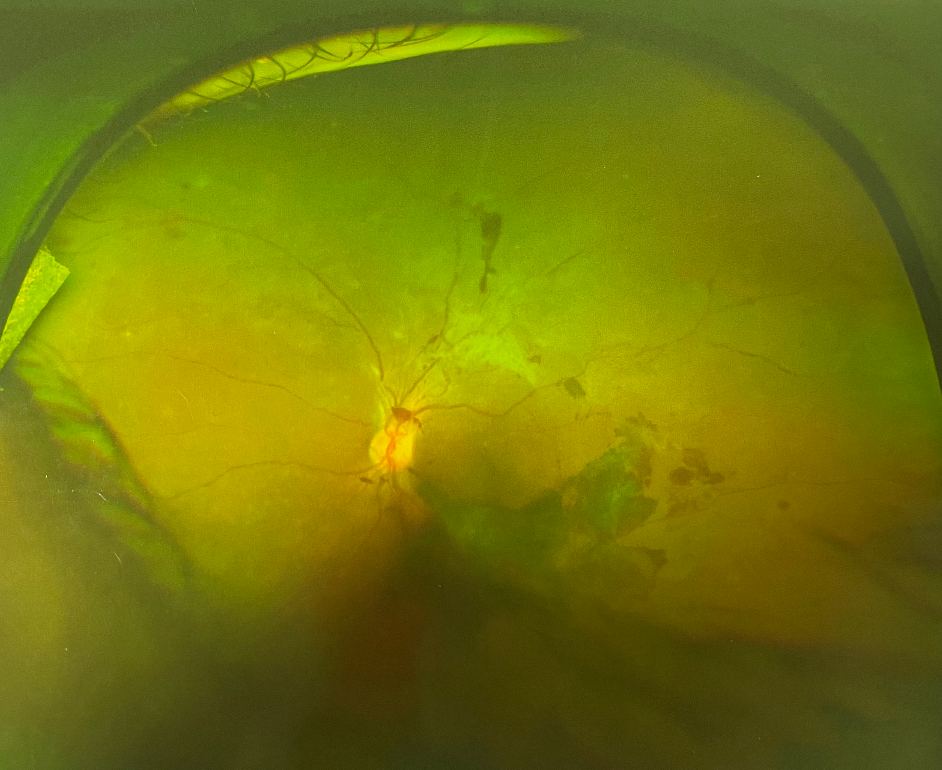

眼底出血是常見的眼科疾病之一,是眼底視網(wǎng)膜血管的病變引起的。正常情況下,血液在人體的血管內(nèi)流動(dòng),不會(huì)溢出,但如果身體出了問題,無論是眼睛局部的問題還是全身的病變,在眼睛血管里流動(dòng)的血液就會(huì)溢出來,溢在視網(wǎng)膜上,這就形成了眼底出血。

造成眼底出血的原因有很多,如果治療不及時(shí)還會(huì)引起失明的嚴(yán)重后果,所以一定要早發(fā)現(xiàn)早治療。

眼部檢查不只是簡(jiǎn)單的檢查視力,而是需要到專業(yè)眼科醫(yī)院進(jìn)行視力、眼壓、眼底照相、眼底熒光血管造影、OCT(光學(xué)相干斷層掃描)等一系列的專業(yè)眼部檢查。

目前多用眼內(nèi)注射聯(lián)合激光治療,以藥物治療為輔。

眼內(nèi)注射主要治療伴有黃斑水腫的患者,治療后大部分黃斑水腫消退,視力提高。

眼底激光治療主要是延緩病情發(fā)展,防治新生血管的產(chǎn)生或消退新生血管,避免更嚴(yán)重的視力下降。